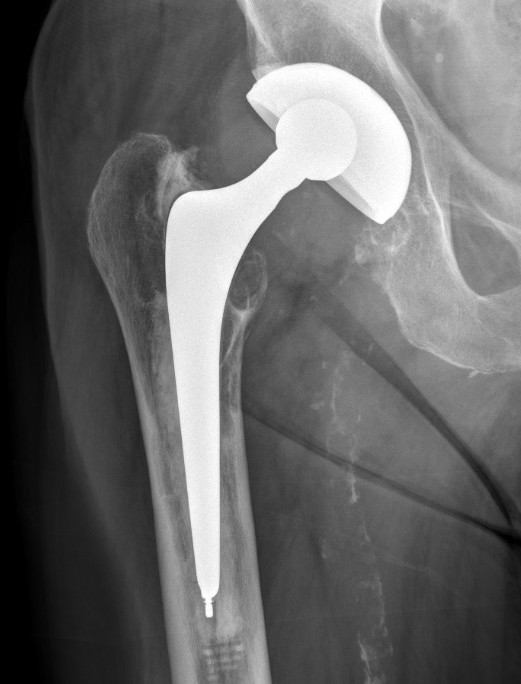

Dual mobility

van Eecke et al Hip Pelvis 2020

- systematic review of constrained and dual mobility in revision THA

- 46 studies and 5,600 hips

- survival: DM 94.7% vs. constrained 81.0%)

- dislocation rates: DM 2.6% vs. constrained 11.0%

- acetabular loosening rates: DM 1.0% vs. constrained 2.0%